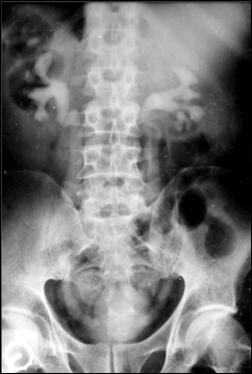

Diagnosticul diferential cu tuberculoza urogenitala

Vezica urinara are contururi greu delimitabile pe cistografie si pacientul are ureterohidronefroza bilaterala.

Figura 57. Vezica urinara mica |

Vezica urinara mica, scleroasa, cu rinichi drept unic chirurgical, uretero-hidronefroza gr I

Figura 59. Vezica urinara "crispata", cu ureterohidronefroza bilaterala. |